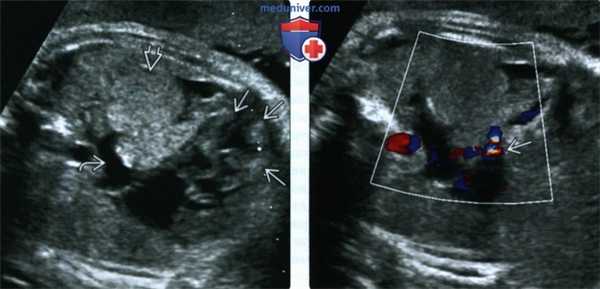

(Слева) УЗИ. Туберозный склероз. Полость ЛЖ заполняет очень крупное образование, выступающее в ЛП и, по-видимому, затрудняющее кровоток. Также в ПЖ определяется несколько небольших образований.

(Справа) То же изображение в режиме ЦДК. Визуализируется обструкция выходного и входного отделов ЛЖ. После рождения ребенка была предпринята попытка хирургического формирования анастомоза в обход ЛЖ, не увенчавшаяся успехом. Подобный исход не характерен для рабдомиомы.